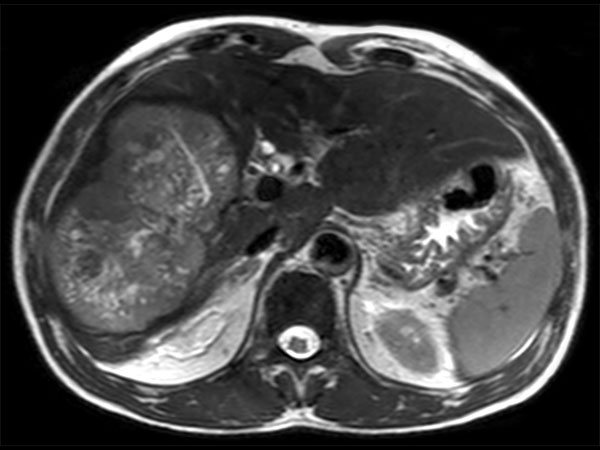

Axial T2w TSE

Axial T2w SPAIR